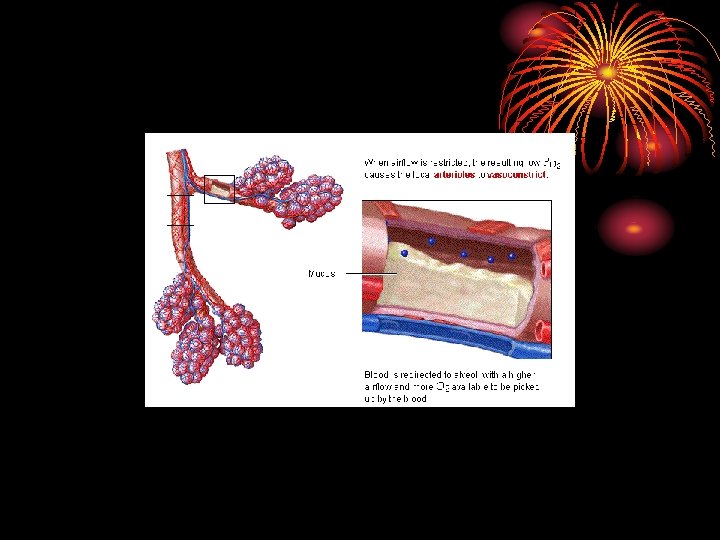

Ventilation-perfusion ratio V/Q • Pulm. alveolar ventilation / perfusion = 4. 2/5. 5 = 0. 8. • Both ventilation and perfusion decreases towards the apex, but the perfusion decreases more, so V/Q increases at the apex (more PO 2 T. B) at apex.